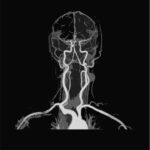

If you are looking for an MR Angiography (MRA) of the Brain then you have come to the right place. With the help of Medifyhome you can get a detailed examination of the brain. We are partnered with NABL and NABH accredited diagnostic centres and labs that offer a wide range of facilities and radiology tests at the most affordable prices available in the market. MR Angiography (MRA) of the Brain is a specialised imaging test that uses magnetic resonance imaging (MRI) to visualise the blood vessels in the brain. This non-invasive procedure provides detailed images of arteries and veins to assess blood flow and detect abnormalities, such as blockages and blood clots. Book your appointment now with Medifyhome to get the best prices for an MR Angiography (MRA) of the Brain , call us at +919100907036 or +919100907622 and schedule your appointment now.